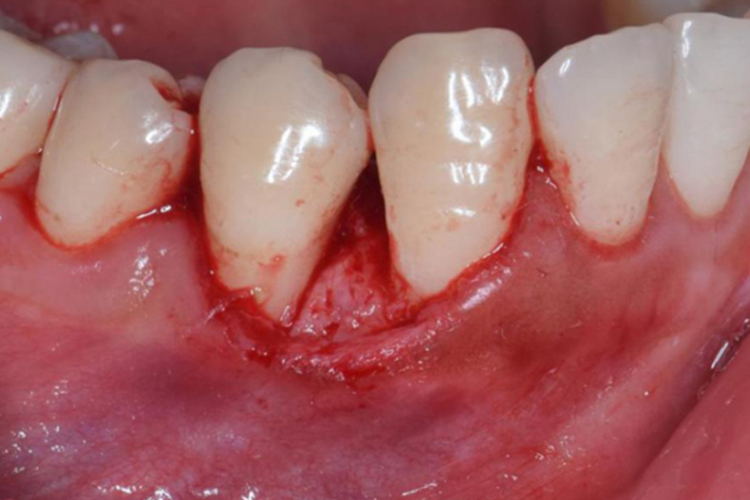

做切口:在肿瘤基底部蒂外0.2-0.3厘米的正常黏膜上做切口,切口深及骨面。

剥离肿瘤:自骨面剥离肿瘤,完整切除。常规需拔出受累牙齿,用刮匙及咬骨钳除去被波及的牙周膜、骨膜及牙槽骨,以防复发。需注意妊娠期牙龈瘤切除可不拔牙及去除牙槽骨。